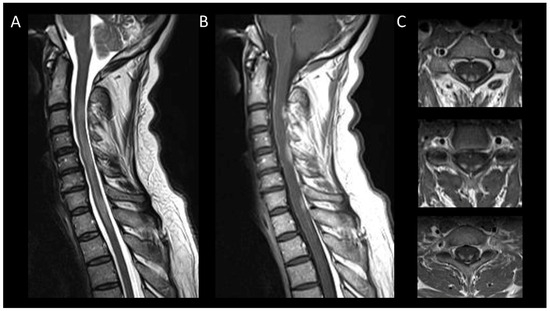

3.1. Inflammatory Myelitis

3.1.1. Short Myelitis

Multiple Sclerosis

Other Inflammatory Causes of Short Myelitis

3.1.2. Longitudinally Extensive Myelitis

Neuromyelitis Optica Spectrum Disorders Positive for Aquaporin-4 IgG

Myelin-Oligodendrocyte Glycoprotein Antibody Associated Disease

Neurosarcoidosis